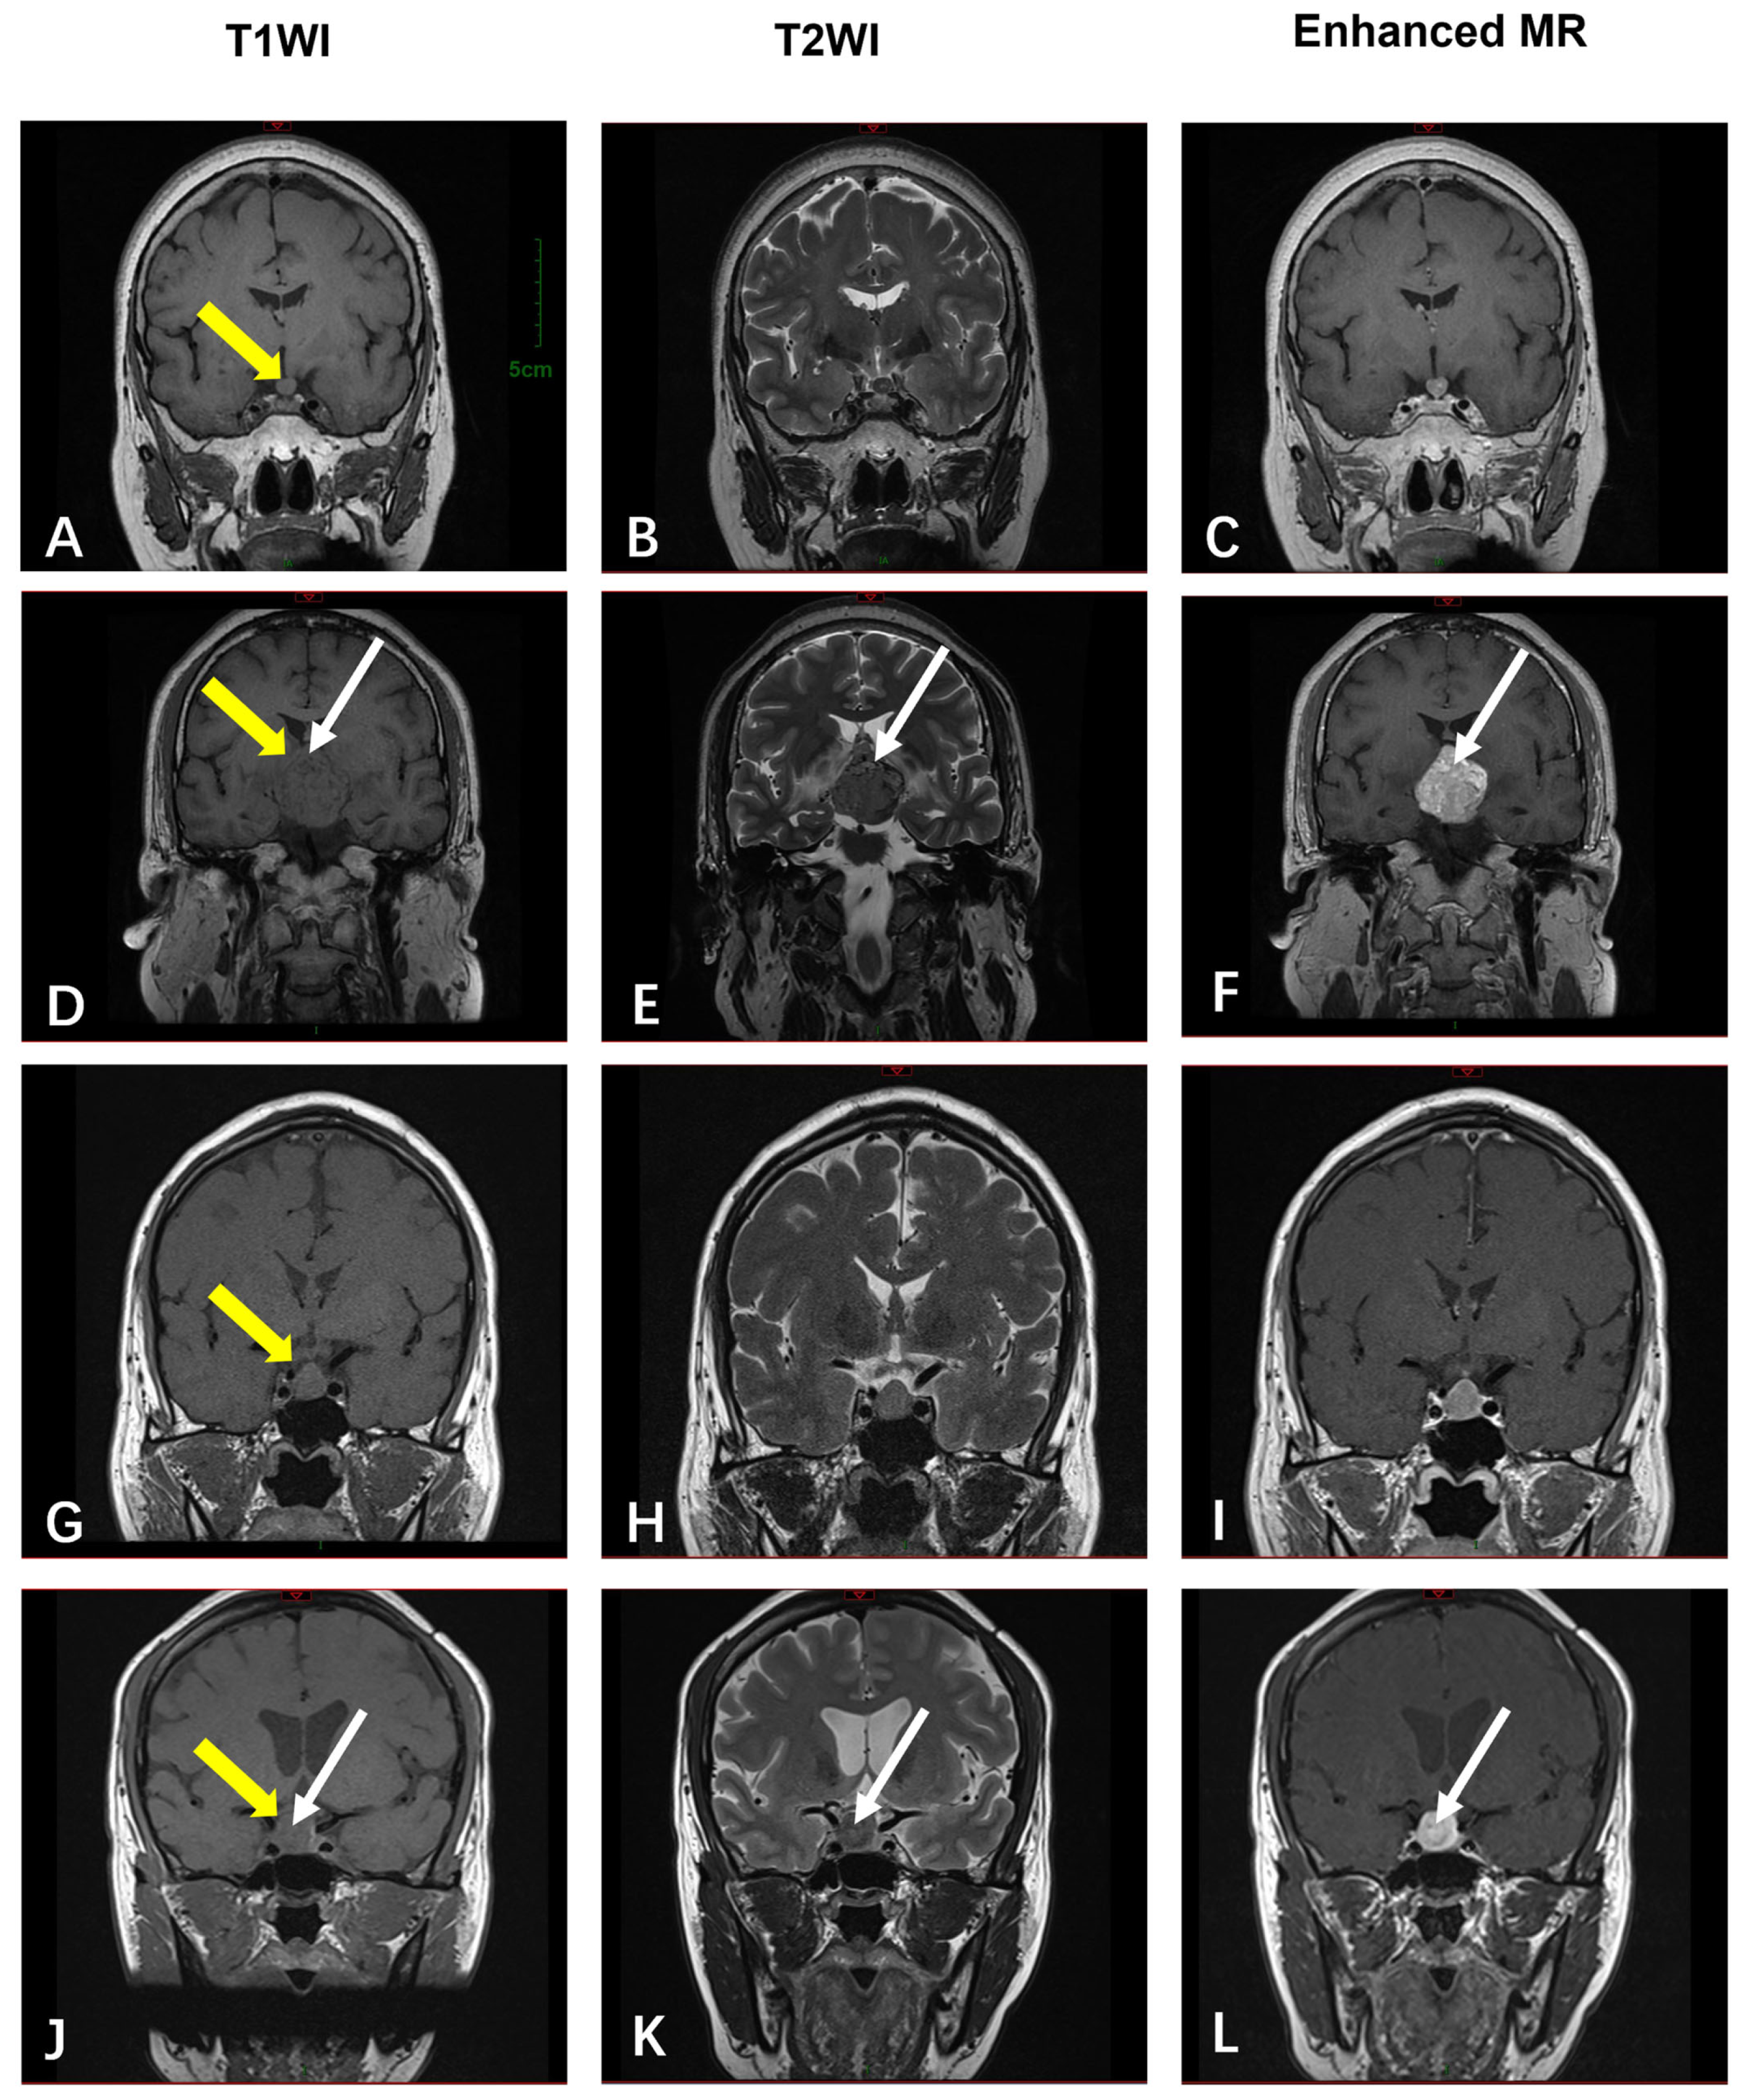

3.2.5. The Sellar Region

| Sellar Region | MRI (n = 4) | T1-isointense; T2-variable (“star-like crack signs” in 50%); heterogeneous enhancement in 50% | N/A (all benign) |